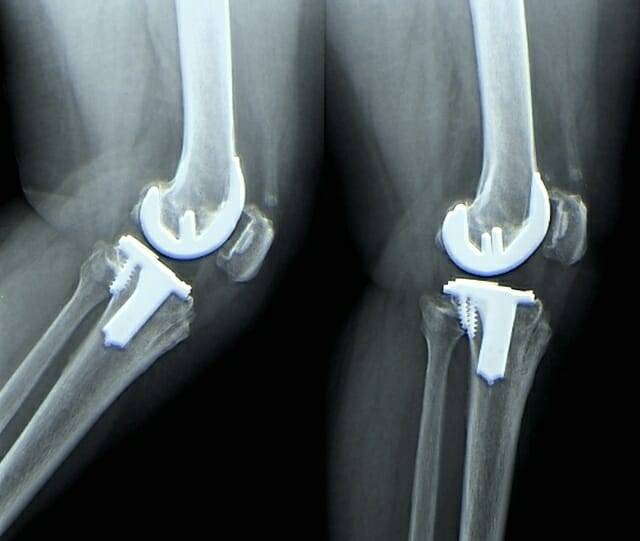

관절염이 악화될 경우 관절에 염증이 생기며 주변 조직보다 pH가 더 산성화되는데, 이때 소재가 젤리처럼 부드럽게 변하면서 내부에 캡슐화된 항염증제를 방출한다.

특히 이 소재는 좁은 pH 범위에서만 반응하도록 설계돼 약물이 필요한 시점과 부위에만 정확히 방출돼 부작용을 최소화할 수 있다고 연구진은 밝혔다. 만약 이 소재가 인공 연골로 활용될 경우, 관절염을 지속적으로 치료해 통증 완화와 항염 효과를 극대화할 수 있을 것으로 기대되고 있다.